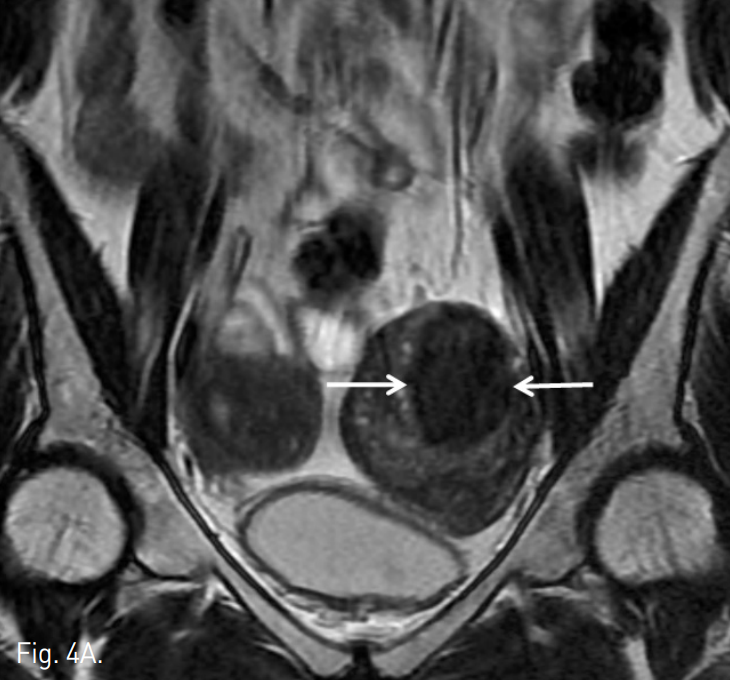

Fig. 4

A, B. T2 weighted (A) and contrast enhanced (B) MR images taken three months after embolization show 44% volume reduction of the left-sided uterus and non-perfusion area in adenomyosis (arrows in A and B).